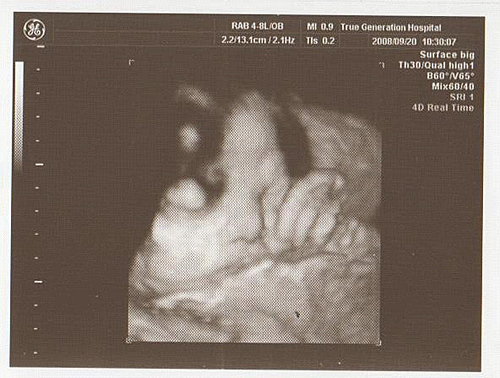

結果今天去產檢

寶寶的體重仍是直線上升

已經3260公克了

整個臉胖嘟嘟的

醫生也說寶寶超重了

生產過程會比較辛苦